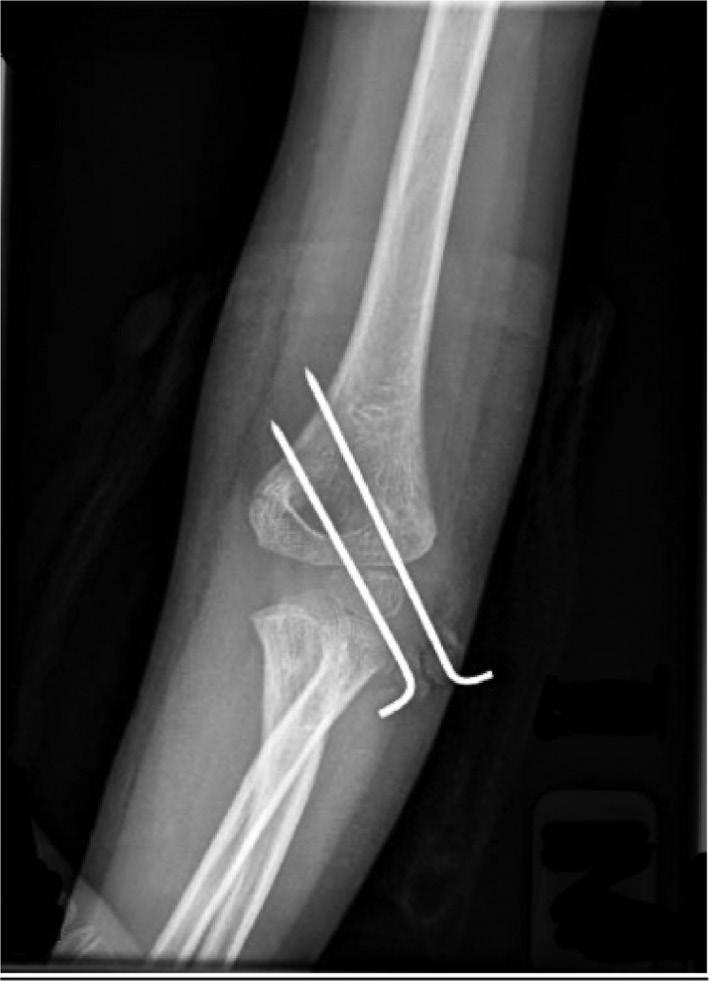

Patients are positioned supine with the affected extremity on a hand table. Reduction is achieved with longitudinal traction, correction of medial/ lateral translational displacement, correction of varus/valgus displacement, and complete flexion with pronation. Once reduced, fixation can be with either 2-3 lateral pins placed in a divergent pattern or a medial pin and one or two lateral pins placed in a crossing configuration (Figure 3).26

Figure 3. In addressing a supracondylar humerus fracture, at least two pins should engage fracture fragments in a bicortical fashion. Pins should be separated by at least 10 mm at the fracture site.

Three lateral pins are typically sufficient to secure Gartland-type III SCHF. While the crossed-pin pattern is mechanically advantageous, medial pin placement is associated with a risk of injury to the ulnar nerve. This risk can be mitigated with a mini-open approach or by driving the pin in with the elbow in extension whilst directly palpating the medial epicondyle. Medial pins are especially useful when the fracture exits proximally in the medial metaphyseal flare.